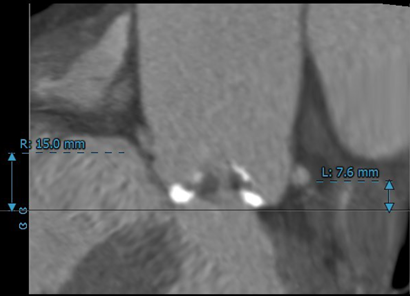

左冠开口高度较低,仅7.6mm,有冠脉堵塞风险;右冠开口15mm,无明显冠脉堵塞风险。